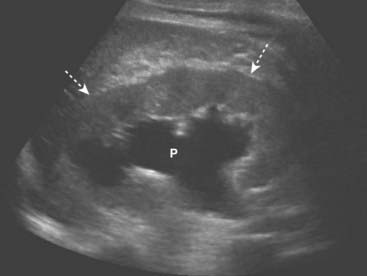

image Hydronephrosis is defined as dilatation of the renal pelvis and calyces.

image The typical appearance of obstructive uropathy is a dilated calyceal system. The echogenic renal sinus contains a dilated, fluid-filled, and therefore anechoic renal pelvis. The ureter may be dilated to the level of the obstructing stone. Severe hydronephrosis may distort the appearance of the kidney (Fig. 19-10).

Figure 19-10 Hydronephrosis, sagittal view, right kidney.

The renal sinus now contains a markedly dilated, fluid-filled and anechoic renal pelvis (P) in this patient with hydronephrosis. The renal parenchyma remains normal in size and echogenicity (dotted white arrows). The patient had an obstructing stone at the ureteropelvic junction.